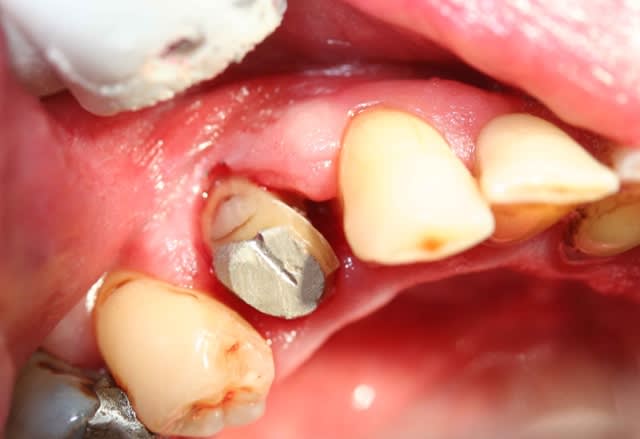

je déterre ce post suite à une consultation de ce matin.

la patiente est une jeune femme, tout ce qu'il y a de plus normal.

les soins ont moins d'un an

bien entendu c'est cassé

voilà, bonne matinée

Sérieusement, pas simple à gérer psychologiquement (cliniquement c'est facile par contre)

2 CVI + tenon , dans ces conditions, on va dire 15 minutes maxi , peut être une matrice tofflemire mais c'est même pas certain.

comment trouver les mots pour expliquer la situation et rester confraternel?

on a tous dans les placards des soins peut être borderline, mais là c'est compliqué à défendre.